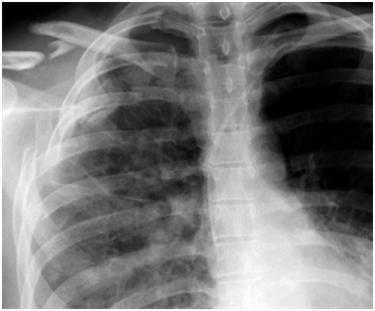

weekly clinical round for undergraduate from 8 to 11 AM during which interpretation of CHEST X rays was done for all cases of cardiothoracic surgery, gived by 2 staf member for 3 months